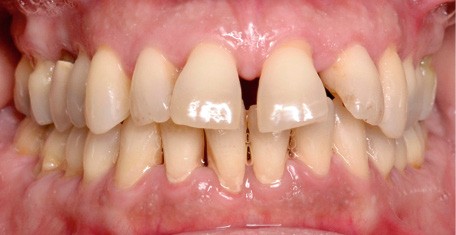

À l’examen endo-buccal (fig. 2), on note une formule dentaire complète (absence des 8) avec présence de restaurations multiples étanches, un bon contrôle de plaque et une parodontite de stade 4 grade C stabilisée [3], des récessions gingivales et des mobilités dentaires généralisées (degré 2, classification de Miller). L’arcade mandibulaire présente une courbe de spee importante avec égression du bloc incisivo-canin. Les milieux inter-incisifs sont alignés, le recouvrement est normal, le surplomb est augmenté à 3 mm et associé à des diastèmes et de la vestibulo-version des incisives maxillaires. Les relations antéro-postérieures canine et molaire sont en Classe I d’Angle.

Les objectifs sont atteints en 30 mois, la patiente est très satisfaite d’un point de vue fonctionnel et esthétique (fig. 10-13). La fonction linguale est rééduquée et la patiente continue sa maintenance parodontale régulière.